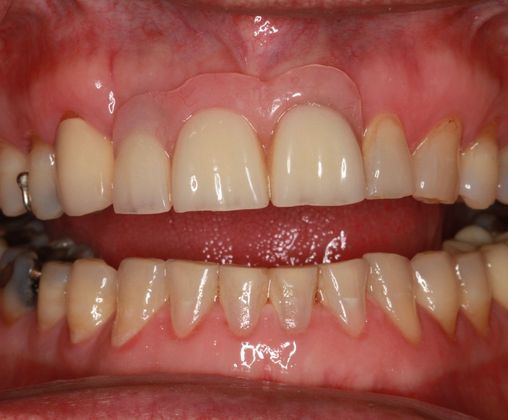

Dental Implants: Case 8

This patient presented after years of wearing a removable partial denture. The patient lost his front teeth from a traumatic event and now wanted a more permanent restoration. Two dental implants were placed and an implant bridge was made in the area. It was decided that two implants would be better than three and would give a more aesthetic result. The patient was very pleased with the final outcome and even more pleased to not have the extra expense of another dental implant.